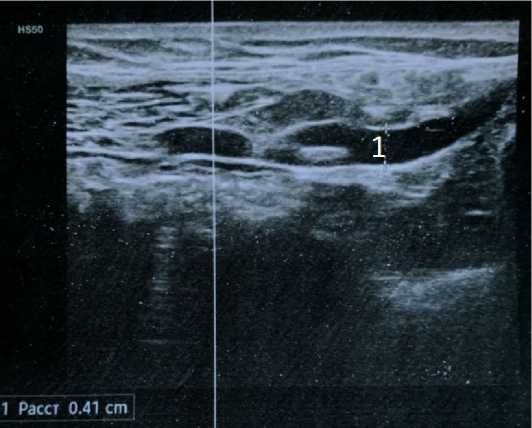

В послеоперационном периоде проводили наблюдение за заживлением раны клинически, по характеру отделяемого по установленному дренажу и при проведении УЗИ. Такой контроль подтвердил необходимость установки дренажа в ране у пациентов с паховой грыжей. Даже при самом тщательном гемостазе в конце операции через 1 сутки в контейнере вакуумного аспиратора накапливалась кровь от 5 до 20 мл и более, которая у пациентов без дренирования раны превращалась в гематому и являлась источником инфицирования раны. Послеоперационные осложнения выявляли и подтверждали при УЗИ.

Рисунок 5. Пациентка Н., 54 года. Диагноз: правосторонняя паховая грыжа. УЗИ паховой области после грыжесечения по способу Лихтенштейна, осложнённого инфильтратом послеоперационной раны: 1 – апоневроз передней стенки пахового канала; 2 – серома; 3 – вид деформированного сетчатого имплантата Figure 5. Patient H., 54 years old. Diagnosis: right-sided inguinal hernia. Ultrasound of the inguinal region after herniotomy using the Lichtenstein method, complicated by postoperative wound infiltrate: 1 – aponeurosis of the anterior wall of the inguinal canal; 2 – seroma; 3 – view of the deformed mesh implant

Рисунок 6. Пациент А., 65 лет. Диагноз: левосторонняя косая паховая грыжа. УЗИ паховой области после грыжесечения по способу Лихтенштейна, осложнённого послеоперационной гематомой: 1 – гематома; 2 – сетчатый имплантат

Figure 6. Patient A., 65 years old. Diagnosis: left-sided oblique inguinal hernia. Ultrasound of the inguinal region after herniotomy using the Lichtenstein method, complicated by postoperative hematoma: 1 – hematoma; 2 – mesh implant

Рисунок 7. Пациентка Н, 44 года. Диагноз: правосторонняя паховая грыжа. УЗИ паховой области после грыжесечения по способу Лихтенштейна, осложнённого послеоперационным инфильтратом: 1 – сетчатый имплантат; 2 – серома с признаками инфицирования; 3, 4 – увеличенные лимфатические узлы; 5 – инфильтрат под апоневрозом; 6 – свищевой ход

Figure 7. Patient H., 44 years old. Diagnosis: right-sided inguinal hernia. Ultrasound of the inguinal region after herniotomy using the Lichtenstein technique, complicated by postoperative infiltrate: 1 – mesh implant; 2 – seroma with signs of infection; 3, 4 – enlarged lymph nodes; 5 – infiltrate under the aponeurosis; 6 – fistula tract